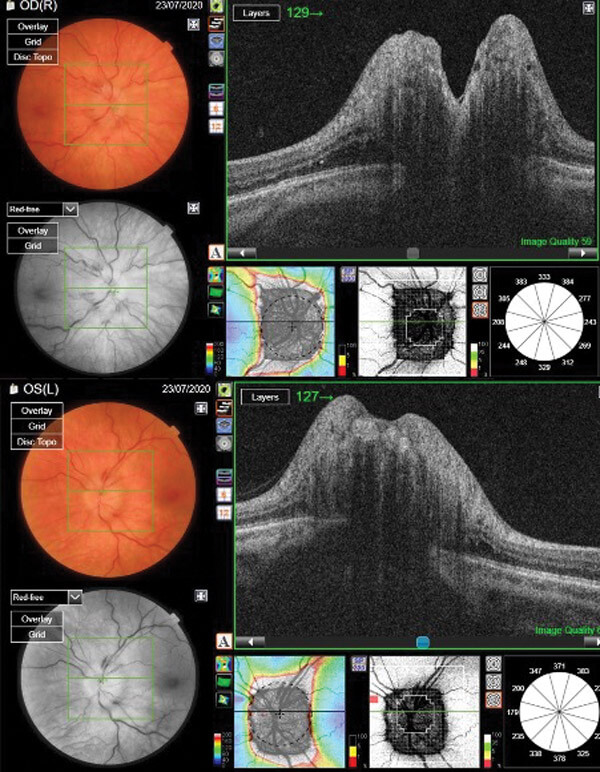

Figure 2: OCT scan of patient with fulminant IIH and bilateral grade 5 optic nerve swelling.

A 35-year-old female presented to the eye emergency clinic with severe headaches, tinnitus and bilateral reduction of vision. Her visual acuity was 6/24 in her right eye and 6/18 in the left. Fundus examination showed severe bilateral optic nerve swelling (Figure 2). She was referred urgently for neuro-imaging (CT / CTv), both were normal, then had an LP which showed opening pressure of more than 40cm of water. She was put on high dose of acetazolamide (500mg TDS), but on follow-up in the neuro-ophthalmology clinic a few days later there was no significant response and her visual functions remained compromised so she was referred for urgent surgical intervention and she had a VP shunt inserted. On follow-up a few weeks later her optic nerve swelling started to reduce (Figure 3) with improvement of her visual acuity, although she developed a nasal field defect in her right eye.

Figure 3: OCT scan of the same patient following VP shunt insertion.